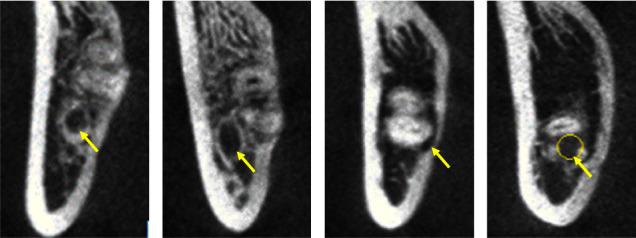

The CBCT imaging data of 260 Korean and Han patients were collected. The patients' genders, ages, impaction types and depths, relative positions between the MTMs and the mandibular nerve canals, and the shortest distances and shapes at the root tips and cortical bones were all recorded and analyzed. All data were compared using the nonparametric test, ordered logistic regression analysis, a chi-square test, and Fisher's exact test.

The relationship between the mandibular canal and the relative position of the MTM differed between Korean and Han patients, mainly in the different types of impactions, and the difference was statistically significant ( < 0.05). The shortest distance between the mesioangular and horizontally impacted mandibular canals and the buccal side of the MTM in Korean patients was less than in Han patients, and the difference was statistically significant ( < 0.05). For horizontal impactions, the probability of cortical bone interruption was 1.980 times greater in Korean patients than in Han patients, and the difference was statistically significant ( < 0.05). The significance threshold was set at 0.05.

There are some differences in the positional relationship between the mandibular canal in the MTM region and the rate of cortical bone disruption between Koreans from the Yanbian area and the Hans. This should gain clinical attention.